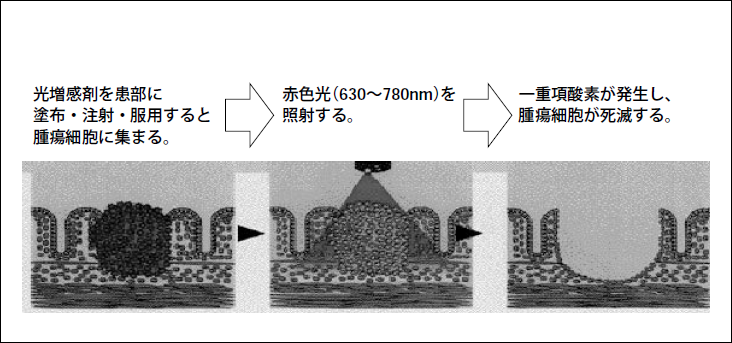

光線力学的治療(Photodynamic therapy、PDT)とは、腫瘍親和性を有する光増感剤を腫瘍組織に特異的に集積させ、特定波長を有する光線を照射することによって生成する一重項酸素によって選択的に腫瘍組織を壊滅する療法である。これまでPDTには光源としてレーザー光が使われているが、治療面積が小さい、装置が高価で大型などの問題点がある。そこで我々は、レーザー光の替わりに新しく開発したメタルハライドランプを用いて、PTDにおけるメタルハライドランプの効果について検討した。

図1 PDTの原理